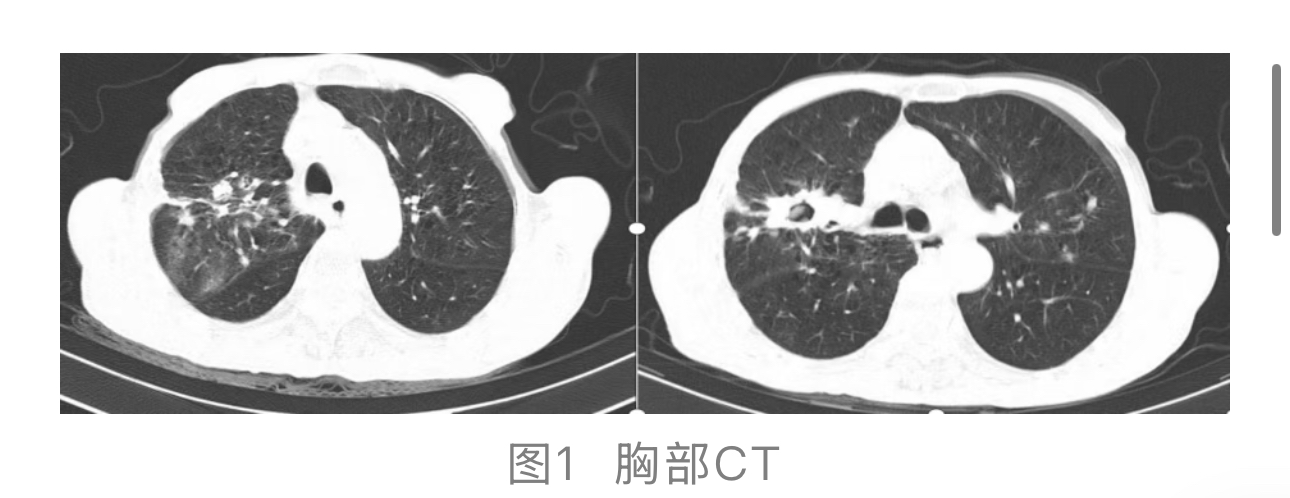

(3)影像学检查:

胸部CT:右肺,左肺上叶见多发结节状,片状,索条状密度增高影,边界清晰,内见空气支气管征,部分病变内见钙化灶,右肺上叶厚壁空洞形成并与支气管相通。双肺多发斑片状模糊影,右肺为著。(图1)